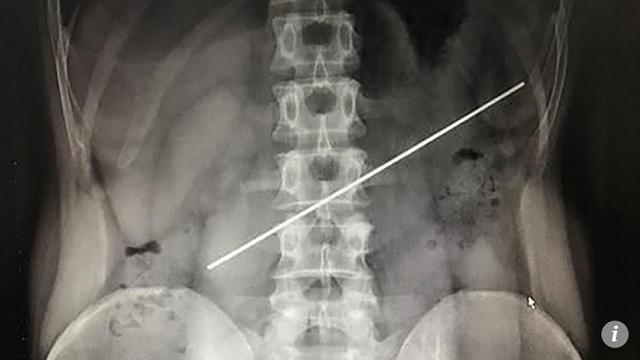

Thanh thép dài 20cm trong dạ dày của bệnh nhân.

Người đàn ông không cảm thấy đau đớn nhưng một năm sau mới, đến bệnh viện để kiểm tra. Ảnh chụp X-quang cho thấy phần cuối thanh thép đâm thủng dạ dày.